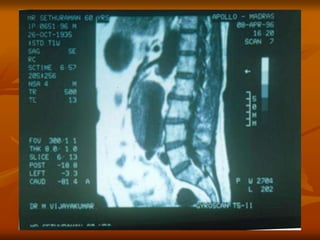

CT Imaging

 Precise test – provides good

images of aorta,aortic

lumen,branch vessels and

adjacent retroperitoneal

structures.

 Shows size and extent of

aneurysm and relation to renal

and iliac arteries.

 SPIRAL CT – 3 dimensional

image.